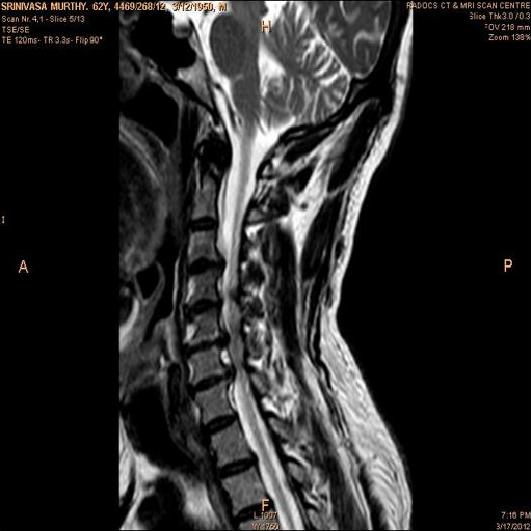

In order to show the proposed method in more detail, the algorithm is tested with other test images. The first row of Fig. 6 shows the original MRI image of thoracic spine with different views. The second row of Fig. 6 shows the same image enhanced using histogram equalization. Third row of Fig. 6 presents the MSR based enhancement scheme. Fourth row of Fig. 6 indicates Chao’s method of image enhancement. Finally, the reconstructed images using the proposed method is shown in fifth row of Fig. 6. Again, it can be seen from the results presented that the image enhancement using the proposed method is superior compared to other methods. This is evident from the image quality assessment presented in Table 1 using AWE and DWE.